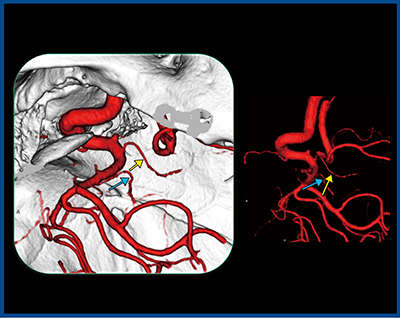

症例5は,61歳,女性,左中大脳動脈瘤である。動脈瘤手術においても血管評価は重要であり,手術では動脈瘤周囲の血管を剥離して動脈瘤の根元にクリップを掛ける必要がある。本症例をAquilion Precisionで詳細に観察すると,動脈瘤の周囲に複数の細い血管が癒着している所見が認められ,この剥離に難渋することが予想された。

実際の手術にて,術前3D-CTAのとおり細い血管が動脈瘤に癒着しており,破裂しやすい動脈瘤突起部も正確に描出できていることが確認された。術前画像でシミュレーションができていたため,ていねいに血管を剥離し,動脈にクリップを掛けることができた。術後の従来CTとAquilion Precisionの画像を比較すると,Aquilion Precisionの方がクリップやその周囲の血管も明瞭に描出されており,術後評価でも十分に有用と考えられる(図6)。

図6 症例5:左中大脳動脈瘤の術後の画像比較